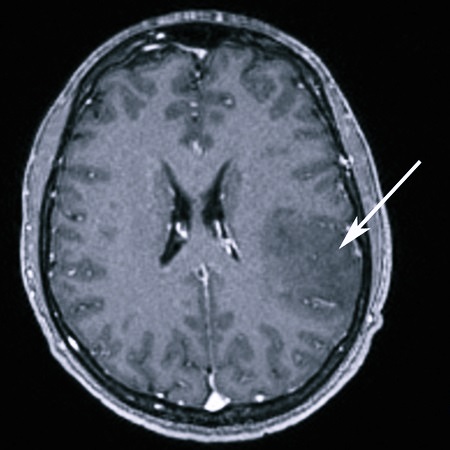

Для точного определения наличия глиомы специалисты рекомендуют проводить магнитно-резонансную томографию (МРТ), которая позволяет визуализировать опухоль и оценить ее характеристики. В некоторых случаях может потребоваться биопсия для подтверждения диагноза. Врачи подчеркивают важность раннего обращения к специалистам при появлении настораживающих симптомов, так как это значительно увеличивает шансы на успешное лечение и улучшение качества жизни пациента.

Важно дифференцировать заболевание от абсцесса мозга, гематомы, эпилепсии, инсульта, других опухолей ЦНС. Сейчас чаще всего назначается МРТ. Это самый современный метод для диагностики. Если ее нельзя провести, могут назначить компьютерную томографию, МСКТ, сцинтиграфию, ангиографию (с применением контраста).

- сканирование при помощи МРТ;